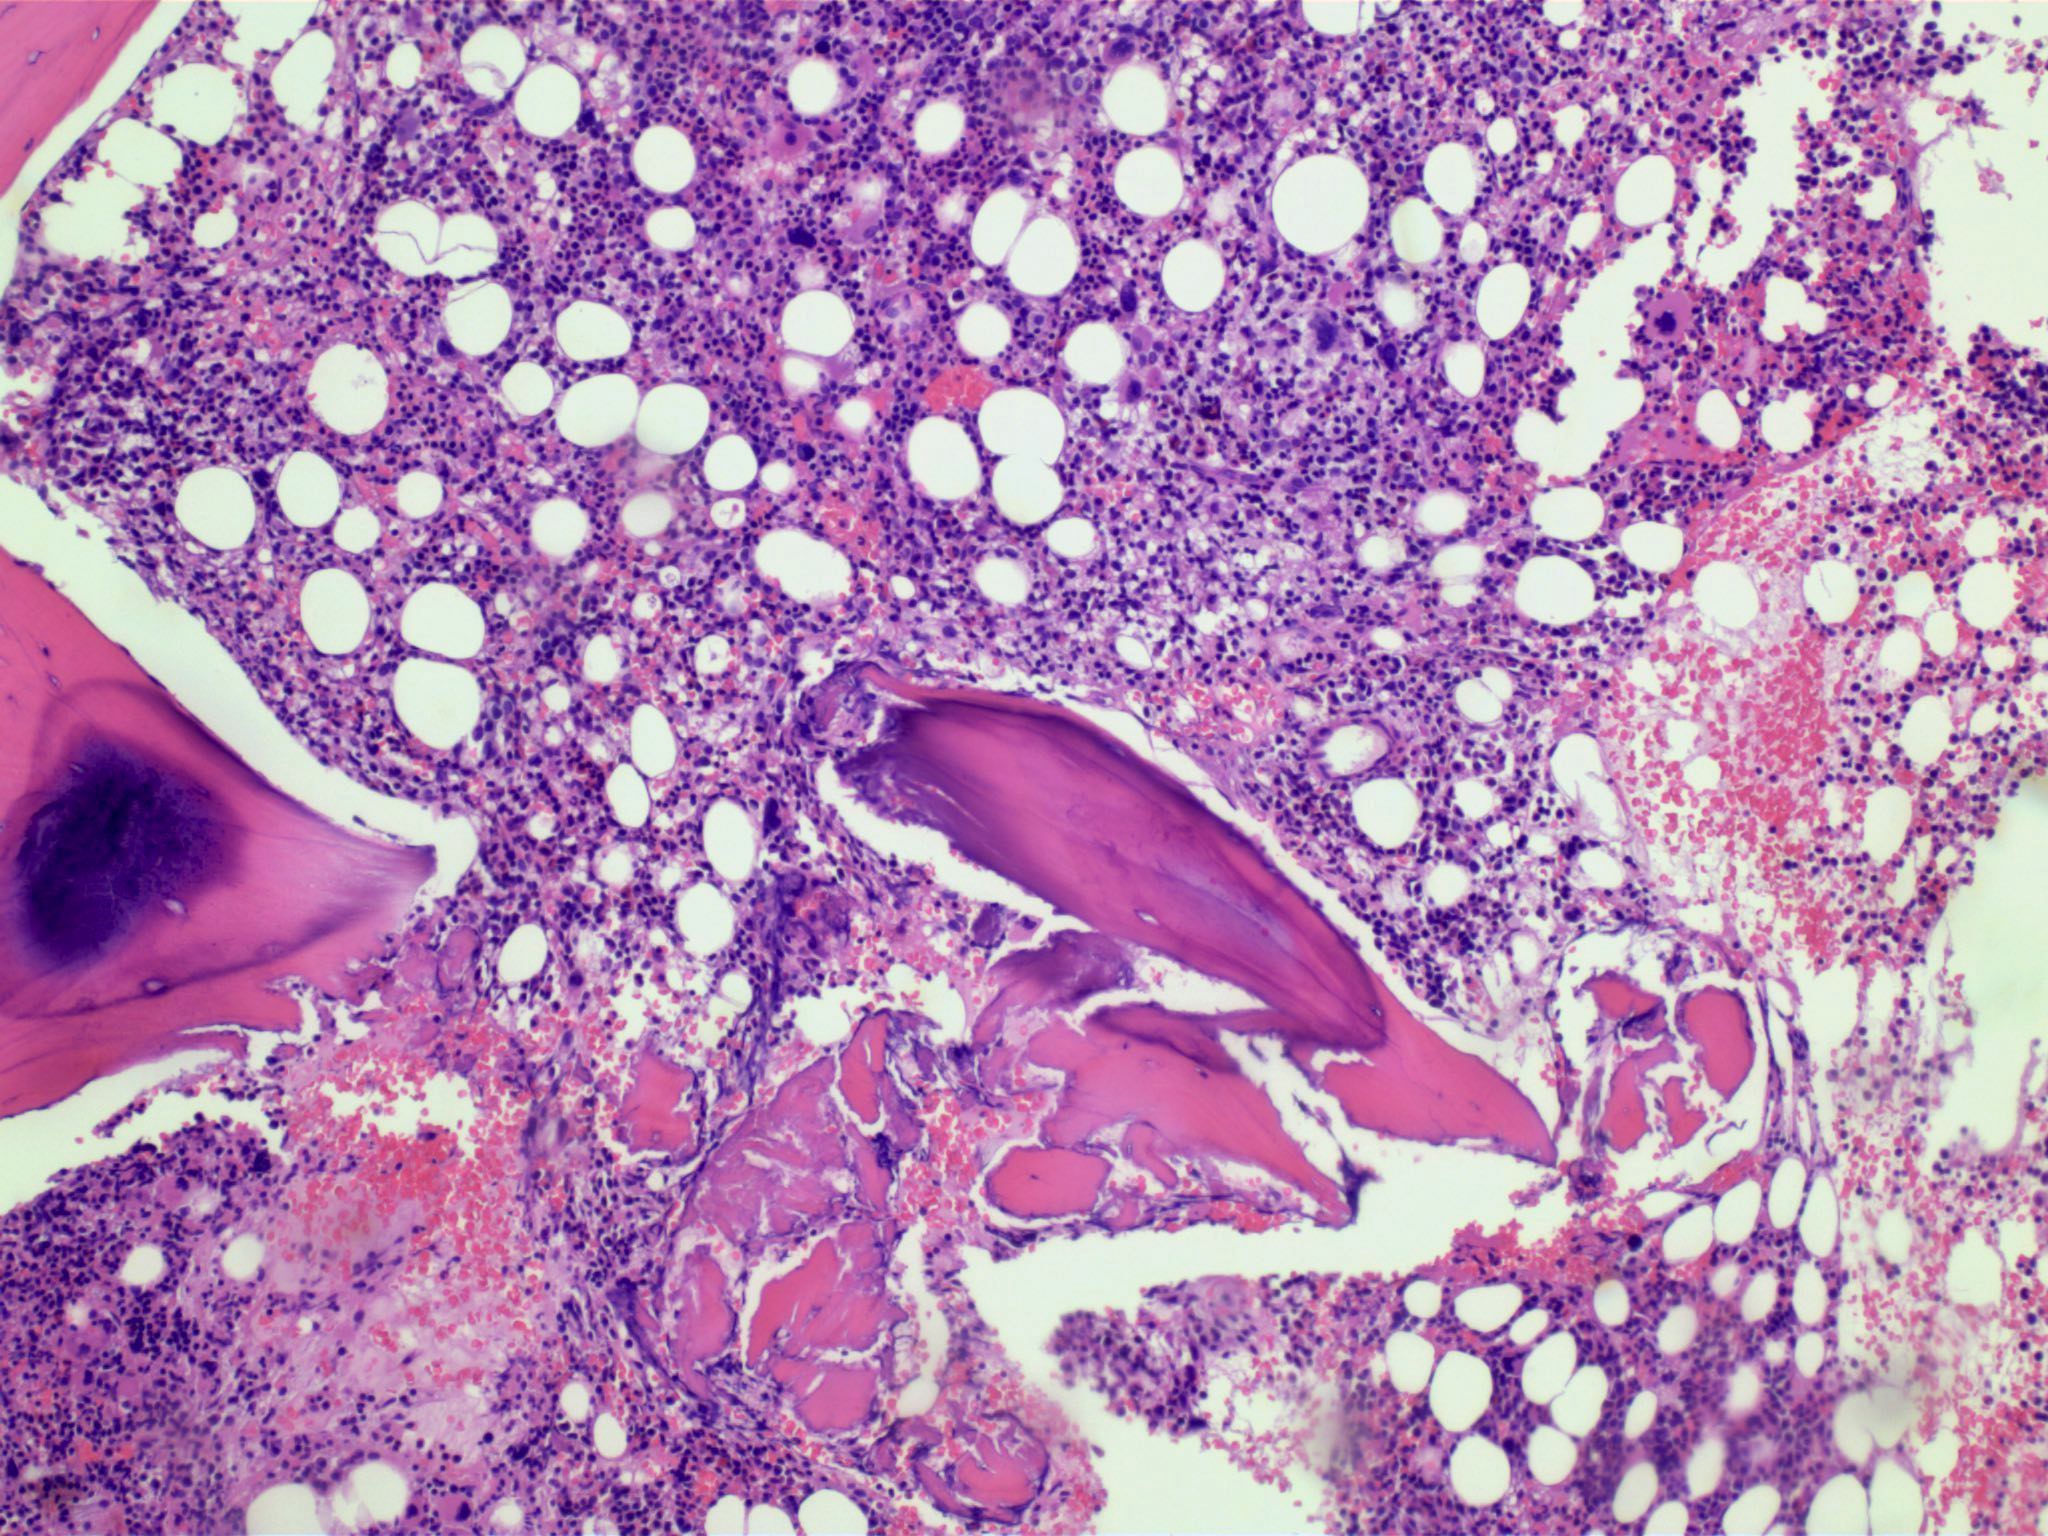

Microscopic (histologic) description

- Bone marrow (Front Oncol 2021;11:778741)

- Hypercellular or hypocellular

- Hypercellular with myeloid lineage predominance

- Dysplasia is seen in at least one hematopoietic lineage

- Percentage of blasts in peripheral blood and bone marrow must be < 20%

- Typically few blasts are seen

- Include promonocytes as blast equivalents

- Bone marrow fibrosis is seen in up to 30%

- Increased megakaryocytes with variable clustering

- Often myelodysplasia-like with small size and nuclear hypolobation

- MDS / MPN with iso(17q) typically shows the myelodysplasia-like megakaryocytes

Microscopic (histologic) images